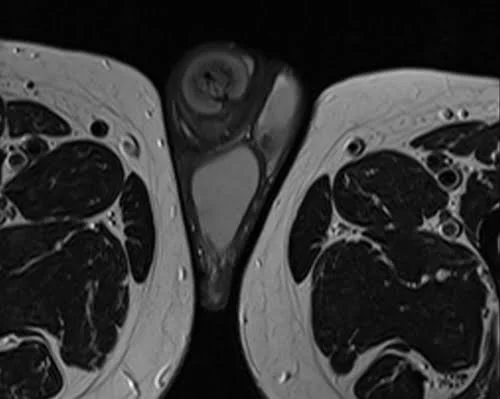

MRI testis sfov axial t2 high res image 1 - MRI